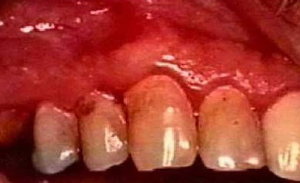

健康的牙龈应该是粉红色、有光泽的,质地坚韧,牙龈沟只有2-3毫米;而发炎的牙龈则会颜色变红变深、肿大疏松,很容易出血,牙龈沟(牙龈与牙颈部连接处形成的空隙)也会加深。牙龈炎实际上就是最轻微的牙周病,其炎症只侵犯牙龈组织,不侵犯其他牙周组织,它主要是由于牙龈周围、特别是牙龈沟内的牙菌斑所导致的炎症反应。

牙龈炎发展为牙周炎,牙周附着逐渐丧失,牙周刺激物越来越多,牙槽骨被破坏。